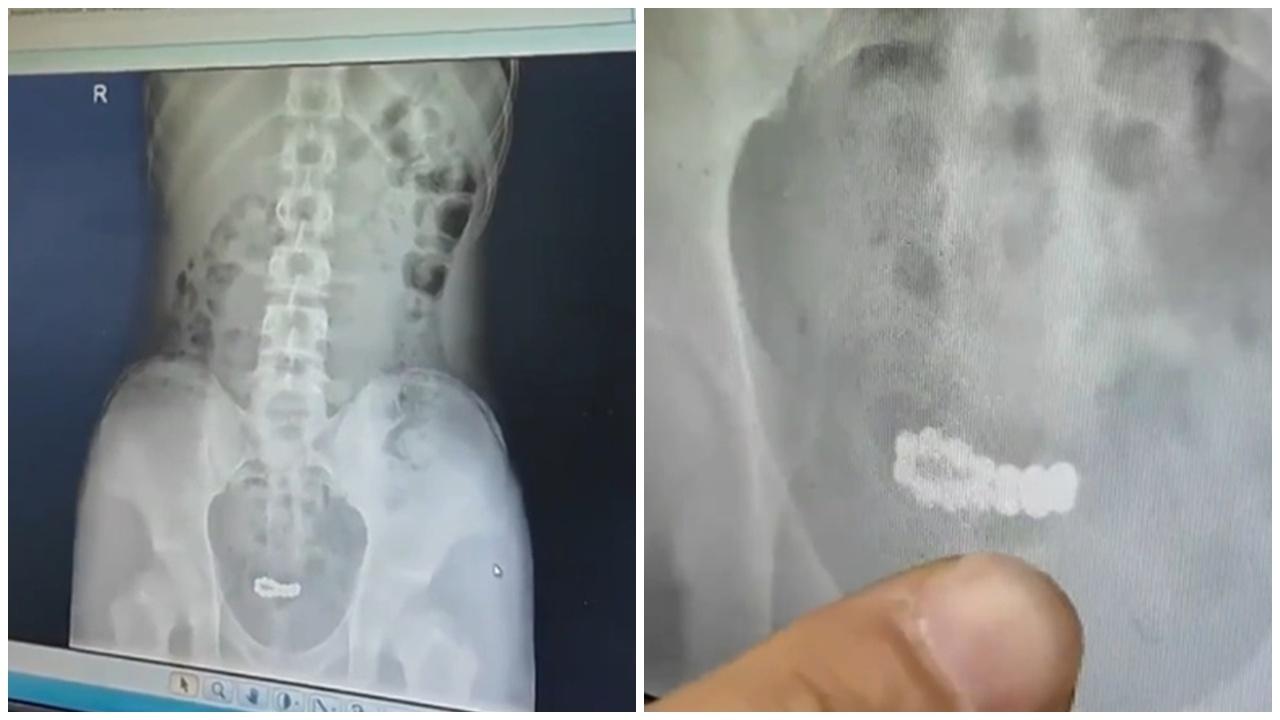

綜合《荔枝新聞》、《新京報》等內地媒體報道,南京一名15歲少年因對身體好奇,將14顆磁力珠塞入尿道,泌尿外科醫生表示,磁力珠雖直徑小於尿道,但取出困難,其金屬材質和強大吸力易造成膀胱損傷。少年就醫時已出現尿頻尿急、腹部疼痛等癥狀,所幸治療及時,最終通過微創手術,成功將磁力珠全部取出。